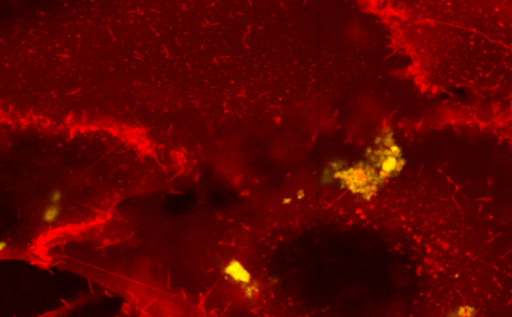

Celice, ki so velike nekaj mikrometrov, in vanje ujeti nanodelci, veliki le nekaj nanometrov, so prostemu očesu nevidni, da jih lahko opazujemo, pa potrebujemo mikroskop. Za spremljanje procesov, ki se v celici dogajajo ob stiku z nanodelcem, se uporablja že nekaj desetletij znana in izjemno uporabna metoda mikroskopije, in sicer fluorescenčna mikroskopija. Celične strukture, kot so mitohondriji ali jedro, prav tako pa tudi nanodelci ne oddajajo svetlobe sami po sebi, kot to počnejo denimo kresničke. Kaj je fluorescenca in kako nam omogoča zaznavanje majhnih struktur?

Glavna omejitev fluorescenčne mikroskopije je prenizka ločljivost, saj delcev, ki so si preblizu, ne moremo med seboj ločiti. Rešitev predstavlja nova vrsta visokoločljivega mikroskopa, to je mikroskop STED, za razvoj katerega je bila leta 2014 podeljena Nobelova nagrada. Visokoločljivi mikroskop pri delu uporabljajo tudi na inštitutu. Kaj je ločljivost in zakaj je mikroskop STED tako uporaben?

Na inštitutu so raziskovali, kako na celice vpliva vrsta nanodelca, imenovana titanov dioksid. Za raziskovalni model so izbrali pljučne celice. Celice nimajo naravnih mehanizmov, s katerimi bi znale tak delec razgraditi, zato ga ovijejo v svojo membrano. Pri tem se celica poškoduje, nanodelec pa sproža vnetje. Kakšne so lastnosti nanodelcev titanovega dioksida, zakaj se uporabljajo in kakšen je njihov vpliv na celične strukture?